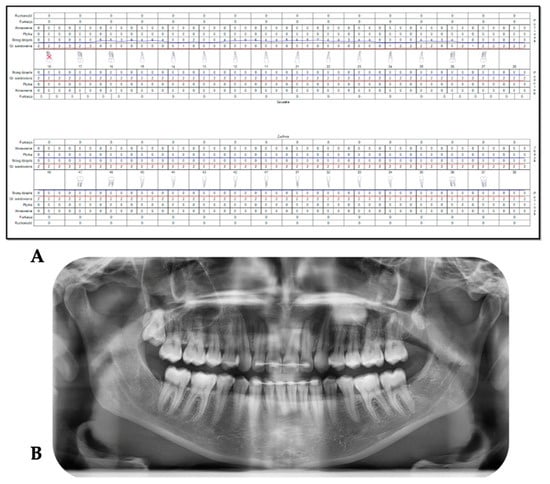

2.4. Outcomes Assessment Measures

2.5. Treatment Description